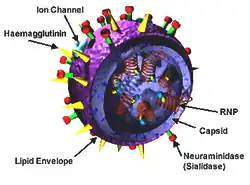

Estrutura, propriedades e nomenclatura dos subtipos

As estruturas dos influenzavirus A, B e C são muito semelhantes entre si. A partícula viral mede 80-120 nanómetros de diâmetro e é aproximadamente esférica, embora possam também ocorrer formas filamentosas.[47][48] Estas formas filamentosas são mais comuns no vírus da gripe C, o qual pode formar, na superfície das células infetadas, estruturas semelhantes a cordas até 500 micrómetros de comprimento.[49] No entanto, apesar destas diferenças na forma, as partículas virais de todos os vírus da gripe apresentam composição semelhante.[49] Os vírus são constituídos por um envelope viral que contém dois tipos de glicoproteínas que envolvem um núcleo central. Este núcleo contém o genoma ARN viral e outras proteínas virais que envolvem e protegem o ácido ribonucleico (ARN). O ARN é geralmente de filamento único, embora em casos especiais possa ser duplo.[48] Ao contrário da generalidade dos vírus, o seu genoma não é um elemento único de ácido nucleico; em vez disso, contém sete ou oito segmentos de ARN de senso negativo, cada um dos quais com um ou dois genes que codificam uma proteína diferente.[49] Por exemplo, o genoma da gripe A contém 11 genes em oito segmentos de ARN, os quais codificam 11 proteínas: hemaglutinina (HA), neuraminidase (NA), nucleoproteína (NP), e as proteínas M1, M2, NS1, NS2, PA, PB1, PB1-F2 e PB2.[50]

A hemaglutinina (HA) e a neuraminidase (NA) são as duas proteínas de grande dimensão no exterior das partículas virais. A HA é uma lectina mediadora da ligação do vírus às células-alvo e a entrada do genoma viral nessas células. A NA participa na libertação de vírus a partir das células infetadas.[51] Desta forma, estas proteínas são alvos para fármacos antivirais.[52] Para além disso, são antígenos para os quais é possível produzir anticorpos. Os vírus da gripe A são classificados em subtipos de acordo com a resposta dos anticorpos à HA e à NA. Os diferentes tipos de HA e NA determinam a distinção "H" e "N" na denominação; por exemplo, "H5N1".[53] São conhecidos 16 subtipos H e 9 subtipos N, embora apenas os subtipos H1, H2 e H3, e os N1 e N2 sejam comuns em seres humanos.[54]